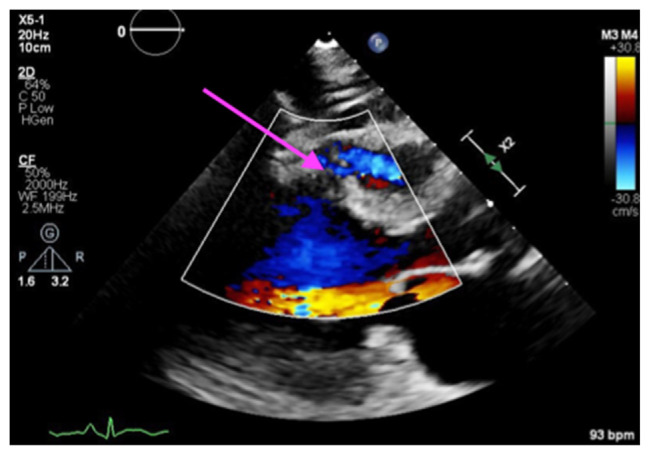

Case presentation: A 91-year-old woman with a history of coronary artery disease had undergone PCI in left anterior descending (LAD) and left circumflex artery (LCX) for a non-ST-elevation myocardial infarction (NSTEMI) 4 weeks prior at another facility, which was complicated by distal wire perforation leading to hemopericardium and the need for pericardiocentesis. She presented with chest pain, and her tests showed ST-segment elevation in leads I, aVL, V2-5, and ST-depression on III, avF, and high troponin levels which were concerning for stent thrombosis. Due to her age and multiple comorbidities, she was managed medically and her code status was changed to do-not-resuscitate/do-not-intubate (DNR/DNI) after family discussion. Echocardiogram revealed a severely reduced ejection fraction and a new mid-inferoseptal VSD detected on readmission. The patient died 4 days later, highlighting the critical importance of timely PCI to prevent severe complications like VSD.